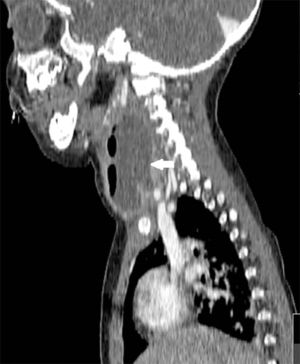

Se han recuperado estudios de imagen de 63 pacientes, a los que se les realizaron 71 pruebas. Las técnicas utilizadas han sido 36 TAC (50,7%), 20 ecografías (28,2%), 8 radiografía lateral de cuello (11,3%) y 7 RMN (9,9%). Al 62,5% (5 de los 8) de los que se realizó radiografía lateral de cuello y al 15% (3 de los 20) de los pacientes a los que se les realizó ecografía, hubo que completarles el estudio con TAC o RMN. A los pacientes a los que se les realizó TAC o RMN no hubo que hacerles más pruebas de imagen. La TAC ha sido empleada fundamentalmente en ACPI de localización más profunda (ARF, APA y APF), mientras que la ecografía fue empleada en ACPI más superficiales (AA y AS) (figs. 1 y 2).

Las técnicas de imagen más utilizadas han sido la TAC y la ecografía, empleadas en un 86% de los casos. Se usó cada una en diferente situación: la TAC preferentemente en abscesos de localización profunda y la ecografía en abscesos superficiales. La TAC se ha usado en el 100% de los APF y en el 75% de los ARF. La ecografía se usó en el 78% de los AS y en el 70% de las AA, siendo, no obstante, la prueba inicial en muchos casos con objeto de evitar radiaciones innecesarias a niños de corta edad14. Aunque la TAC supone una prueba que requiere colaboración del paciente (puede precisar sedación) e implica radiación del niño, en nuestra opinión es la prueba de elección ante ACPI de localización profunda, si hay mala respuesta al tratamiento o ante la sospecha de complicaciones y es, además, la herramienta más útil para la planificación de la cirugía3–5. La radiografía lateral de cuello, bastante utilizada en los servicios de urgencias, se ha usado solo en 8 ocasiones, todas en ARF, y en nuestro caso con una clara tendencia a la disminución en su uso. Por otro lado, en los últimos años estamos empleando más la RMN tanto como herramienta diagnóstica como para control radiológico ante la sospecha de persistencia de un ACPI tras la cirugía, evitando así radiaciones a los niños.